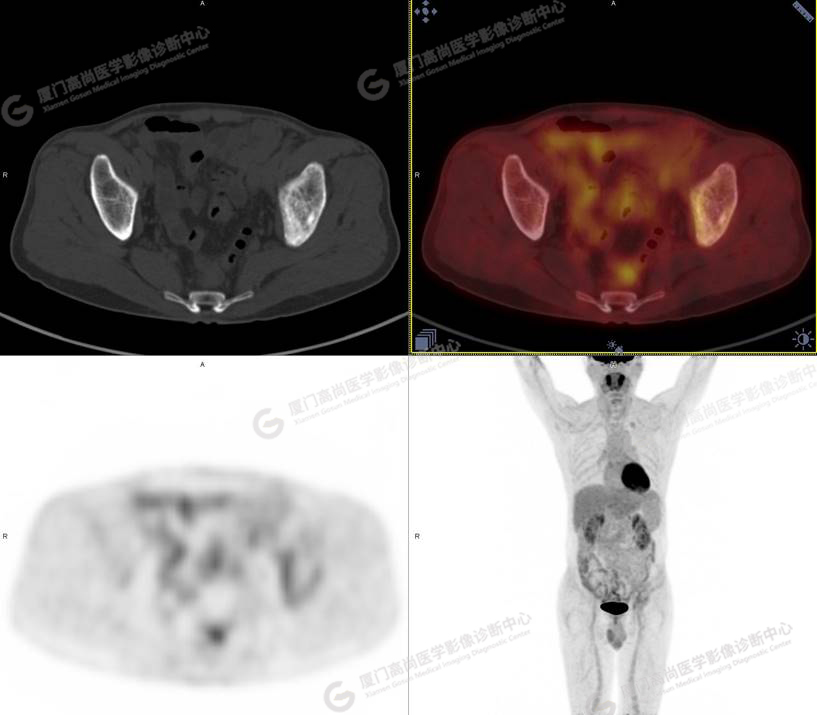

病史摘要1

60歲的L先生,因“左側(cè)臀部疼痛伴行走困難3月余”就診,外院核素骨顯像示:左側(cè)髂骨顯像劑增加,考慮惡性病變可能。同時實驗室檢查發(fā)現(xiàn)腫瘤指標(biāo)糖類抗原724稍增高。談癌色變!驚恐的L先生選擇了腫瘤檢查的核武器——PET/CT以探明虛實。

PET/CT檢查

PET/CT所見:左側(cè)髂骨、髖臼及恥骨骨質(zhì)密度不均勻增高,CT值約594Hu,邊緣模糊,放射性攝取輕度增高,SUVmax 2.79,周圍軟組織未見明顯異常。